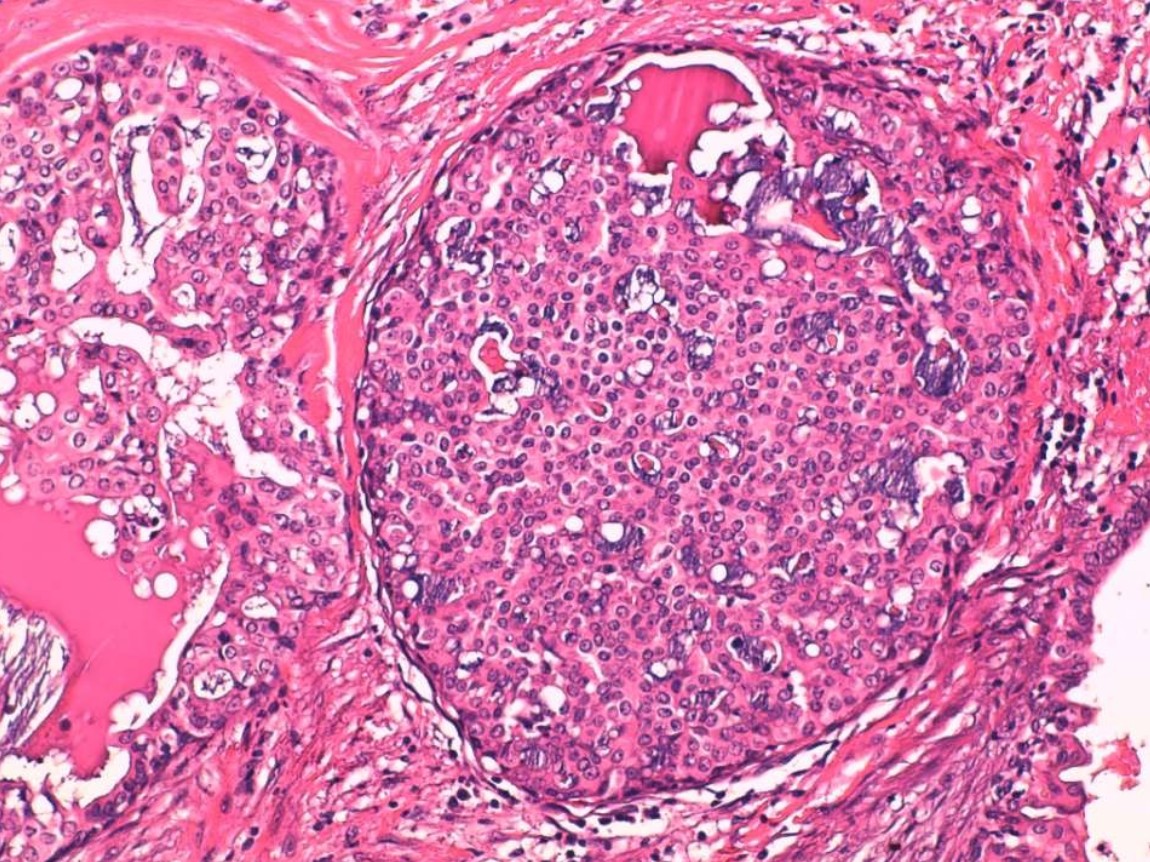

Mujer de 76 años con tumor indoloro en glándula parótida, de crecimiento lento. Se realizó resección quirúrgica de la lesión.

Pieza quirúrgica glándula parótida

1.- De acuerdo con las fotomicrografías, ¿Cuál es su diagnóstico?

a) Carcinoma mucoepidermoide.

b) Adenocarcinoma, NOS.

c) Carcinoma poco diferenciado.

d) Carcinoma intraductal.

e) Carcinoma secretor.